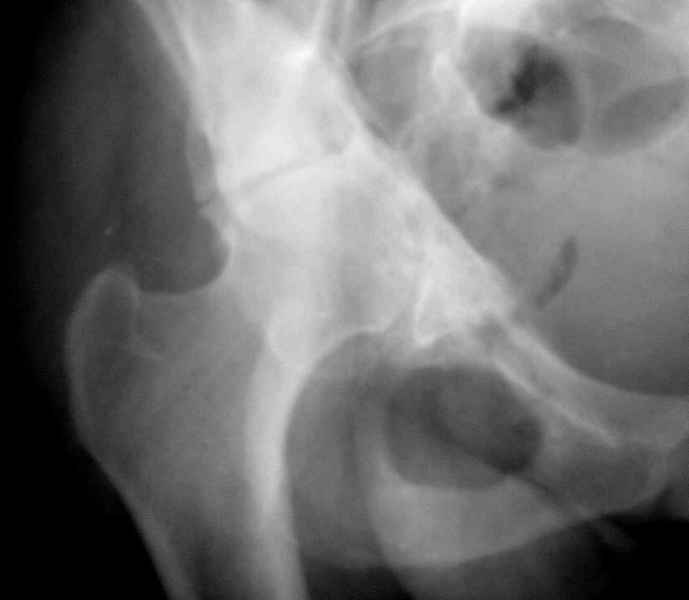

Ув.коллеги,нужен совет по представленному случаю. Пациентка, 50лет. В 2003 году в результате дтп получила перелом вертлужной впадины. 1.5 месяца находилась на скелетном вытяжении, в дальнейшем до 10 месяцев после травмы ходила без опоры на конечность. Вернулась к труду, но в 2006 году перешла на инвалидность и была поставлена в областную очередь эндопротезирования. В данный момент уже находится в отделении, но, судя по рентгенограммам и данным КТ, сращения на уровне перелома не произошло. Что предпочесть? 1.Остеосинтез с костной пластикой и последующим эндопротезированием. 2."Октопус". 3.Кольцо Мюллера. Заранее благодарен за ответы и ценные замечания.

при более внимательном анализе КТ, передняя колонна выглядит сросшейся, остается синтезировать заднюю?Похоже был низкий двухколонный перелом или перелом передней с задним полупоперечником?